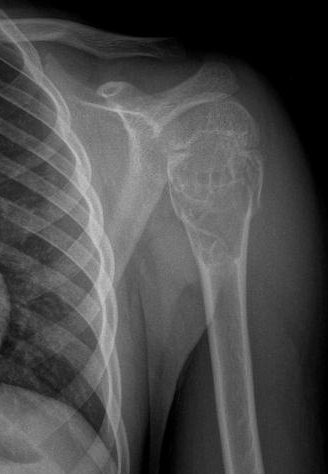

Şimdiye kadar anlattıklarımız kemik yada yumuşak dokunun kendisinden primer olarak kaynaklanan lezyonlardı. Metastazlar ise vücutta var olan kanserli bir dokudan (ör: akciğer kanseri, meme kanseri, böbrek kanseri yada prostat kanseri gibi) ayrılan kötü huylu hücrelerin kan yolu ile kemiklere gelmesi ve burada kitleye neden olmasıdır. Metastazlar genellikle orta-ileri yaş grubunun rahatsızlıklarıdır. Burada hasta büyük oranda kanser olduğunu zaten biliyordur yada kanser tedavisi almaktadır. Örneğin akciğer kanseri olduğu bilinen bir hastada son zamanlarda başlamış olan kalça, bacak , omuz, dirsek yada bel ağrıları ön planda metastaz oluştuğunu akla getirir (resim-24). Metastazlar hızlı ilerleyen kötü huylu lezyonlardır. Tedavileri çabuk şekilde yapılmalıdır. Aksi halde şiddetli kemik ağrıları ortaya çıkar ve sonunda patolojik kırık meydana gelmesi kaçınılmaz olur. Bu durumda tedavi daha da güçleşecektir.

Resim 25

Kemik metastazlarının tedavisinde radyoterapi yada cerrahi tedavi ön plandadır. Eğer hastada patolojik kırık yada patolojik kırık tehditi yoksa radyoterapi tek başına yeterli olabilir. Ancak patolojik kırık gelişmişse yada kırık gelişmek üzereyse (patolojik kırık tehditi) cerrahi uygulanmalıdır. Amaç, hastanın ağrılarını dindirmek ve bir an önce günlük aktivitelerini kazandırarak hayata geri döndürmektir. Ameliyatta tümörlü alan çıkartılır ve oluşan kemik defekti ise implant kullanılarak giderilir (resim-25)..